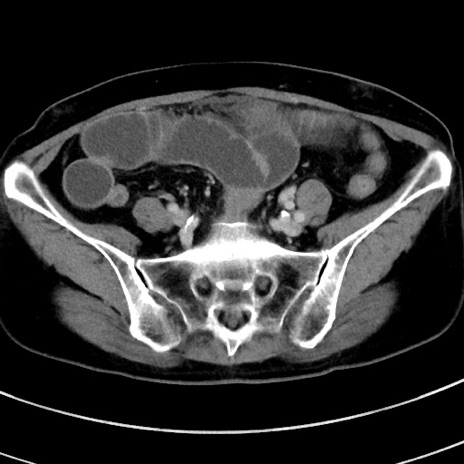

症例9(横断像)

【症例】 60歳代女性

【主訴】むかつき、みぞおちの痛み

【現病歴】3日前よりむかつきがあり、食事がとれない。

【既往歴】糖尿病

【身体所見】発熱なし、心窩部圧痛軽度あるも、腹膜刺激症状なし。

【データ】WBC 7400、CRP 1.92